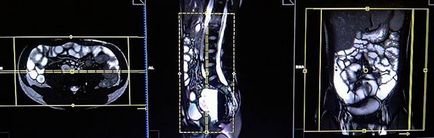

Tervezés koszorúér szeletek axiális síkban; blokk helye keresztirányban hasüregben, amint az ábrán látható. Ellenőrizze a helyét a blokk a 2 másik síkon. Ezek között a szakaszok, hogy teljesen befedje a teljes hasüreget elölről hátrafelé hasfal. A látómező (FOV) elegendőnek kell lennie, hogy fedezze a has és a medence a gyomor, hogy a szint a fancsonti. Annak megakadályozása érdekében műtermékek GDV kell használni fázist túlmintavételezésre (túlmintavételezés). Fontos, hogy a beteget a levegőt-hold alatt képrögzítő csomagokat. (A mi osztály, azt utasítják a pácienseket be és ki kétszer, mielőtt „be és tartsa vissza a lélegzetét” elején a scan).

Tervezés koszorúér szeletek axiális síkban; blokk helye keresztirányban hasüregben, amint az ábrán látható. Ellenőrizze a helyét a blokk a 2 másik síkon. Ezek között a szakaszok, hogy teljesen befedje a teljes hasüreget elölről hátrafelé hasfal. A látómező (FOV) elegendőnek kell lennie, hogy fedezze a has és a medence a gyomor, hogy a szint a fancsonti. Annak megakadályozása érdekében műtermékek GDV kell használni fázist túlmintavételezésre (túlmintavételezés). Fontos, hogy a beteget a levegőt-hold alatt képrögzítő csomagokat. (A mi osztály, azt utasítják a pácienseket be és ki kétszer, mielőtt „be és tartsa vissza a lélegzetét” elején a scan).

Tervezés tengelyirányú szeleteket a koszorúér síkban; blokk helye keresztirányban hasüregben, amint az ábrán látható. Ellenőrizze a helyét a blokk a 2 másik síkon. Ezek a szakaszok teljes mértékben meg kell terjednie a teljes hasüreget és a medence a gyomorból az a szint, a fancsonti. Annak megakadályozása érdekében műtermékek GDV kell használni fázist túlmintavételezésre (túlmintavételezés). Tájékoztassa a beteget, hogy lélegzet-visszatartás során képrögzítő csomagokat. (A mi osztály, azt utasítják a pácienseket be és ki kétszer, mielőtt „be és tartsa vissza a lélegzetét” elején a scan).